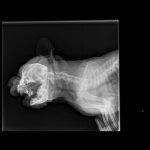

Снимки хорошие, качественные, но совершенно не информативные. На этих пленках патология не определяется. Но здесь нет снимка, который нужен обязательно - поясничный отдел позвоночника в прямой проекции (такой, как 3-й, но только не шея, а поясница).

Нет,наоборот.Собака сначала стала немного наклонять голову вправо.Когда были на консультации у окулиста,то он обратил внимание на это ,сказал,что есть какие-то изменения в области шеи.Я отсутствовала дома 2 недели.Приехала,собаку вообще не узнала.Крен головы вправо стал еще сильнее,передние ноги как-то ослабли.Она идет,может споткнуться,упасть.Сходили,сделали рентген.снимок.Поставили диагноз:атланто-аксиальная нестабильность шейного отдела,спондилоартроз. Проколола 5 дней:актовегин,папаверин,комбилипн,мидокалм,дексаметазон. Пока делала уколы и еще дней 5 после этого собаке стало легче,а потом опять вернулись к тому, что было.На консультации врач сказал,что дальше просто колоть преднизалон. Я уехала к другому врачу,тот сделал снимки,которые я Вам отослала.Сказал, что диагноз не подтверждает,на пальцах показал, что со спинным мозгом все нормально.С помощью какой-то процедуры (бумаги на работе)обнаружил перфорацию барабанной перепонки.Выписал лечение:цефтриаксон,циклоферон,цебролизин(колола 2 дня,стало хуже),комбилипен.В уши-изотик.Сказал,что может быть у собаки был инсульт.Собаке от лечения хуже.Вот такие дела.